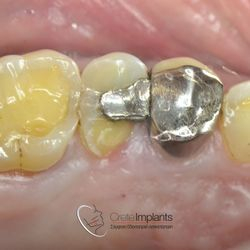

Αποκατάσταση Κατάγματος Οπισθίου Δοντιού

Ο ασθενής προσήλθε στο ιατρείο με κάταγμα του υπερώιου φύματος του άνω δευτέρου προγομφίου.

Αφαιρέθηκε η παλιά έμφραξη αμαλγάματος και προετοιμάστηκε κατάλληλα το δόντι.

Έγινε νέα έμφραξη νανο-υβριδικής σύνθετης ρητίνης τελευταίας γενιάς (HerculiteXRVUltra/Kerr) και το δόντι απέκτησε ξανά το σχήμα και την αντοχή που είχε πριν σπάσει.